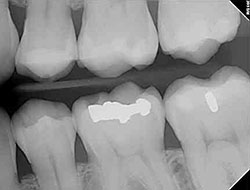

Before & After Gallery

Seeing real results can make all the difference when choosing your dental care provider. That’s why we proudly showcase a selection of before-and-after cases that reflect the work we do every day. From cosmetic smile makeovers to restorative treatments, these transformations speak for themselves.

Each case tells a story — of regained confidence, improved function, and a happier, healthier smile. Our gallery is just a glimpse into what’s possible when personalized care meets technical expertise. We’re proud of what we’ve accomplished for our patients, and we look forward to helping you achieve your own smile goals.